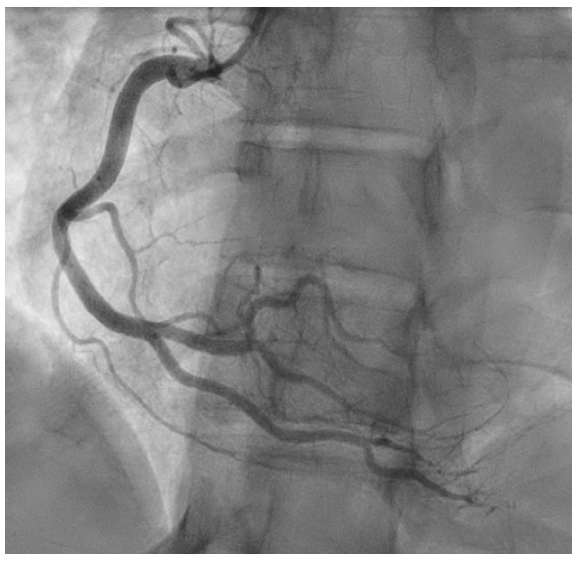

心电图显示:II、III、aVF、V4-V6、I和aVL导联ST段压低,aVR导联ST段抬高伴前间壁q波(图1)。经胸超声心动图显示射血分数保留为55%-60%,无室壁运动异常,中重度二尖瓣反流。左心导管检查显示冠状动脉管腔轻微不规则,而右心导管检查显示充盈压低,心输出量和心脏指数保持正常,右心房压力为0 mmHg,肺毛细血管楔压

为5 mmHg,肺动脉压力为22/7 mmHg,心输出量/心脏指数为4.98/2.83(图2和3)。

图3 冠状动脉造影显示右冠状动脉轻微管腔不规则。